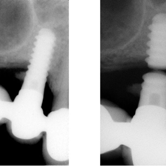

Movilidad del implante

La movilidad del implante es un signo de que el implante no se ha integrado correctamente con el hueso.

Los pacientes notan que el implante se mueve al morder o tocarlo.

El tratamiento incluye la evaluación y, en muchos casos, la extracción del implante móvil y la preparación para uno nuevo.